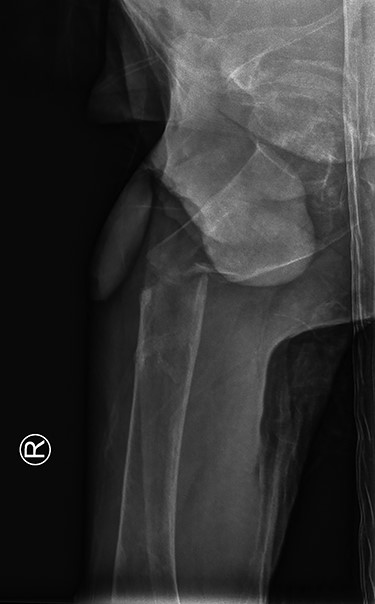

Our patient was discharged from the hospital 14 days after the surgery. The long hospital stay was mostly due to the management of the renal Fanconi syndrome. He was able to mobilize with crutches at time of discharge. The in-hospital stay was without complications. Eight weeks postoperatively our patient returned to our outpatient clinic. Full mobilization was possible and there was a full range of motion. Conventional imaging showed an adequate position of our hybrid osteosynthesis (Fig. 3) and an almost completely healed fracture site.

Post-operative anterior–posterior view: DHS osteosynthesis with intramedullary bone enhancement.